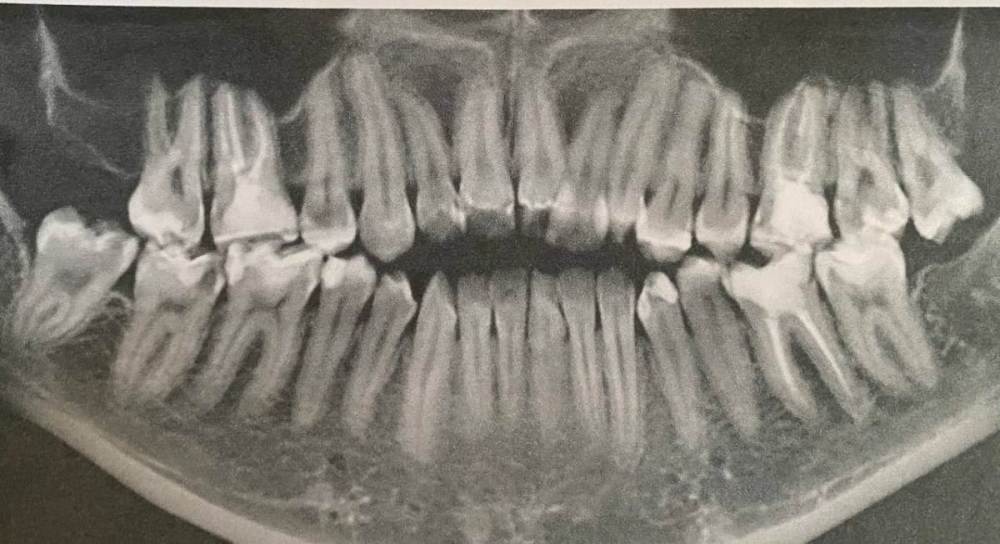

Здравствуйте. В начале марта я сходила на прием, была пролечена (депульпированна) верхняя правая шестерка. После установки временной пломбы в течение двух недель не прекращались ноющие ощущения, поэтому было решено с врачом перелечить зуб. Зуб перелечили, но ноющие боли по-прежнему остались. Зуб не реагирует на холодное/горячее, не шатается, однако реагирует на постукивания.

Была у лора, в одной пазухе есть полип. Может ли он влиять на зуб? Также была у окулиста и невролога с целью исключения патологии тройничного нерва. С этим все в порядке.

Два дня назад треснула эмаль зуба и врач хочет поставить все-таки временную коронку. Я пока сомневаюсь и честно говоря не знаю, что делать, потому что эти странные ноющие ощущения в зубе по-прежнему актуальны. Да и как ставить коронку на зуб, который болит от того, что по нему стучат?...

Была уже у трех врачей, но все говорят, что зуб запломбирован нормально и четкого ответа никто дать не может.

Буду благодарна за любую помощь и ответ. photo_2023-08-09_18-14-31.thumb.jpg.e23f86db67c6866262d362dc6a8b8242.jpgphoto_2023-08-09_18-14-29.thumb.jpg.b2e19e72b9027bf4e4a44185f0ca97e4.jpgphoto_2023-08-09_18-14-25.thumb.jpg.afbef81bf80ad897dc7ffd28efc2453a.jpg

photo_2023-08-09_18-14-28.jpg